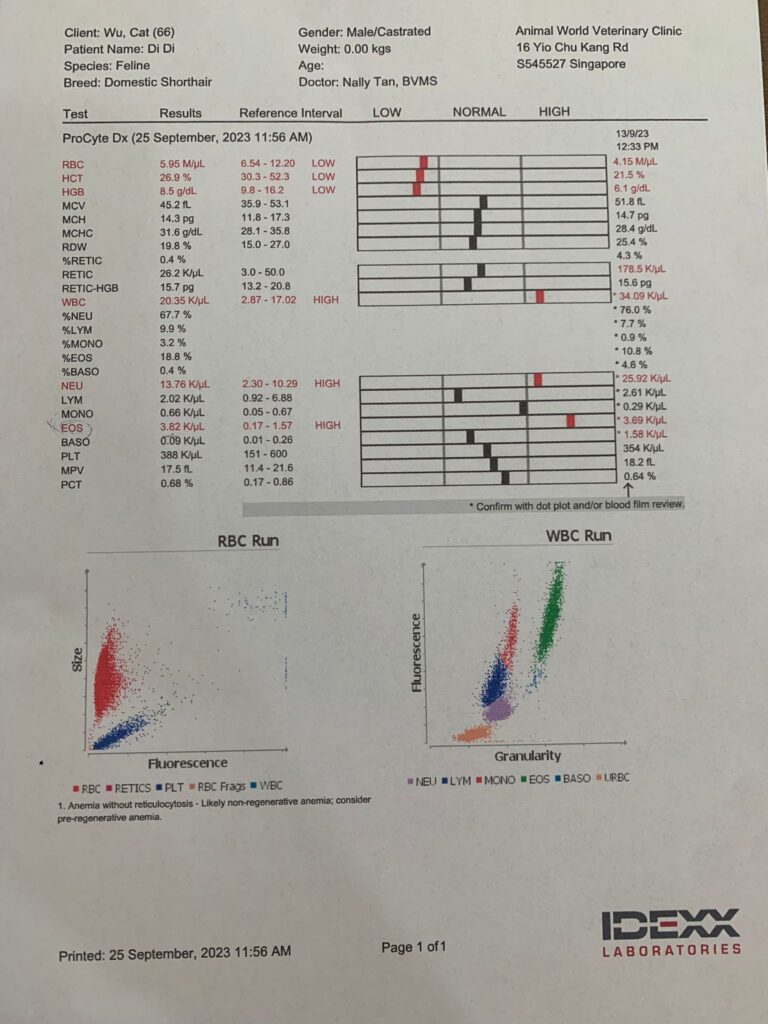

25 Sep 2023

11Am+: 4.23kg – gain 740g in 12 days cos eating well but this morning I serve he did talk away but did eat the aixia oldie and etc b4 we leave house for Dr Nally

Can hear gallop rym – consistent w the hr taken 204. Bp average 191. But clinic damn noisy cos of hacking sound above.when the sound stop rehear again, the heart ok. Anyway last time taken pro bnp le, negative.

To take Cbc. Blood taken from his left jacular – easy and steady.

Cbc out: Eos high again – dr wants him to be dewormed. Hct 26.9%, going up, wbc 20.35 going down doxy to continue for total 21 days.

Back and I Subcut him, his body looks big N hard and muscular. Erm ….

Dr wanna me to use Azithromycin on him, Erm I think no bah.